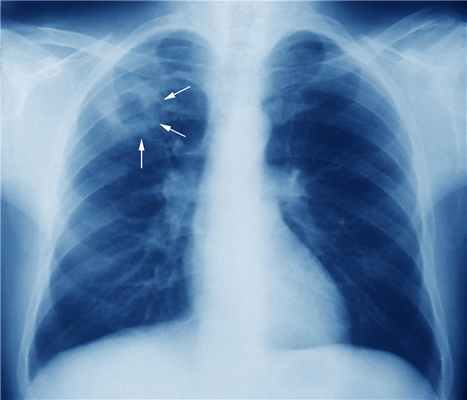

Подозрение на туберкулёз лёгких возникает при обнаружении изменений на обзорной рентгенограмме грудной клетки.

Для улучшения визуализации показано проведение спиральной КТ. Однако ни один рентгенологический признак не считают патогномоничным.

При подозрении на активный туберкулёз лёгких необходимо проведение рентгенологического исследования независимо от срока беременности. При рентгенографии у беременных используют средства, которые сводят к минимуму возможность лучевого повреждения плода.

Основные заболевания, с которыми следует дифференцировать туберкулёз лёгких, — очаговая пневмония и новообразования. Для уточнения диагноза туберкулёза внелёгочной локализации используют МРТ, ультрасонографию, эндоскопические методы.